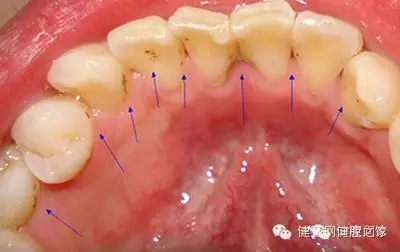

牙垢也叫牙菌斑,是附著在牙齦冠部、頸部及牙縫間的污垢。牙垢主要是食物殘?jiān)?、口腔黏膜脫落的上皮、唾液及?xì)菌混合而成。牙垢久積,容易鈣化成牙結(jié)石。牙垢沉積的多少、快慢,因人而異,與口腔衛(wèi)生習(xí)慣、食物成分、咀嚼習(xí)慣、牙齒排列及機(jī)體代謝情況有關(guān),最快可形成于潔牙后的48小時(shí)。

2. 牙周疾病。牙垢久積,容易形成牙結(jié)石,牙石的存在會(huì)妨礙口腔衛(wèi)生,促使菌斑更多地形成,牙石本身也會(huì)吸附更多的細(xì)菌和毒素,造成牙齦充血、水腫,產(chǎn)生牙齦炎、牙周炎等問題;